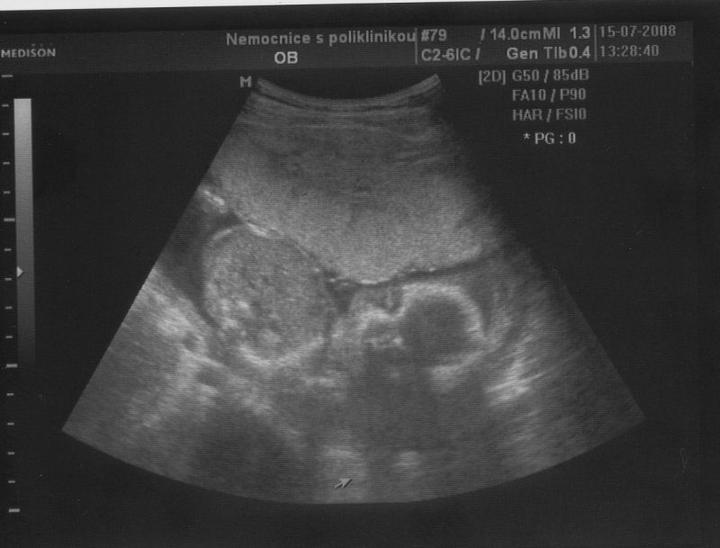

Doktor mi začátkem listopadu 2007 vysadil HA z důvodu zdravotních potíží,dávali jsme si tedy pozor a čekali,zda potíže ustoupí,ale 31.prosince 2007 mi manža řekl,že by chtěl miminko,byla jsem z jeho návrhu vykulená,ale byla to překrásná představa a tak jsem souhlasila..Od 8.ledna 2008 jsme se tedy začali snažit o miminko,začala jsem pít kontryhel a zobat Calibrum babyplan,aby mému tělu nic nechybělo 🙂 Nechávali jsme tomu volný průběh,ani jeden z nás na to nijak nepospíchal,nevím,proč jsem si říkala : Do roka se to snad povede 😀 A 29.3.2008 jsem měla pozitivní testík,sama jsem nechápala,jak brzy se to povedlo 🙂 Byla jsem neskutečně šťastná a stále jsem 🙂 Termín porodu dle MS 5.12.2008 a dle utz ve 12.tt 30.11.2008 Už od začátku jsem tušila,že čekám kluka a tak hned z první kontroly v 5.tt jsem si koupila modré bačkůrky pro štěstí,které se mnou chodili na každou kontrolu 🙂 Od 15.tt mi začalo celkem hodně tvrdnout břicho a chvilkama to bylo velice nepříjemné,na další kontrole,to jsem byla 18+4 , jsem to doktorovi řekla,ten mi pověděl,že se mu to vůbec nelíbí a tak mě poslal na utz,na utz jsem čekala 2 hodiny a můžu říct,že to byli nejhorší 2 hodiny v mém životě,tolik jsem se o miminko bála,ten strach,že něco není v pořádku byl opravdu k nevydržení..Přišla na mě řada a tak jsem tedy šla do kabinky a následně na lehátko na utz,pan doktor konstatoval,že všechno vypadá v pořádku a že se nemám bát,předepsal mi magnezium a že by to mělo pomoct,navíc koukám na ten utz a povídám panu doktorovi,to co tam vidím jsou kouličky? 😀 A on že jistě,že si myslel,že už to dávno vim,když se tak krásně ukazuje 😀 ,můj doktor mi řekl,že zřejmě porodím předčasně,což mě celkem vyvedlo z míry..Ale jsem optimisticky naladěnej človíček a tak jsem Honzíkovi vysvětlovala,že v bříšku musí ještě zůstat..Ve 20.tt jsem šla na velkej UTZ,kde mi opravdu řekli,že Honzík je zdravej a opět Honzík ukázal,že je 100% chlapeček 😀 Ve 26.tt jsme jeli na 4D utz do Liberce,tam se Honzík ukázal zas,no za celé těhu se nestalo,že by se na utz neukázal aa neroztáhl nožičky,máme malýho exibouše 😀 Ve 30.tt mě čekal další UTZ,vše v pořádku,Honzík už byl hlavičkou dolů a vážil 1600g ..Ve 35.tt mě doktor opět kvůli tvrdnutí břicha poslal už do ambulance,aby se o mě starali už tam.. Ten den jsem strávila v nemocnici 7hodin,fakt děsný !!! 2 hodiny čekání u mého doktora,ten mě tedy poslal už do nemocnice,takže jsem musela na UTZ,tam jsem čekala 2 hodiny,pak na natáčky,tam jsem čekala hodinu a pak na ambulanci a tak jsem čekala zas dvě hodiny ☹ Na UTZ ve 36.tt měl Honzík už 2600g ..